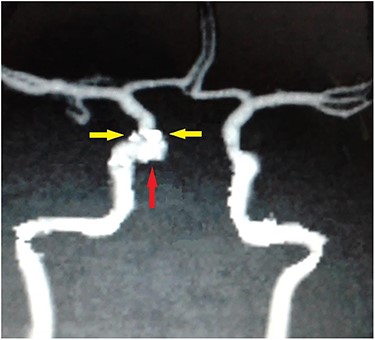

Computed tomography (CT) of the paranasal sinuses and angiography were requested on an urgent basis, which confirmed a diagnosis of pseudoaneurysm in her right CCA, adjacent to retained pellets (Figs 1–4). Also, her hemoglobin dropped from 11.5 to 8.4 gm over a 6-month period. Afterwards, she was referred to the interventional radiology department. She underwent stenting and coiling of her right internal carotid artery after which no further epistaxis happened for an uneventful year of follow-up.

Carotid angiography showing small gun pellets (yellow arrows) and pseudoaneurysm (red arrow) of the right CCA.